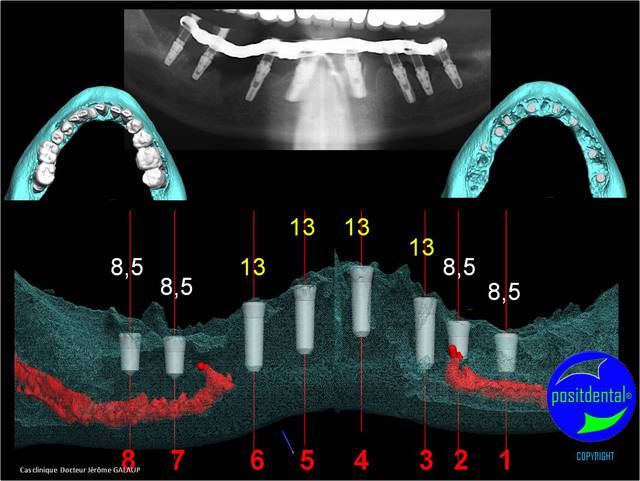

chirurgie à venir

3D maxillaire inférieur et photo

Mci - Eugenol